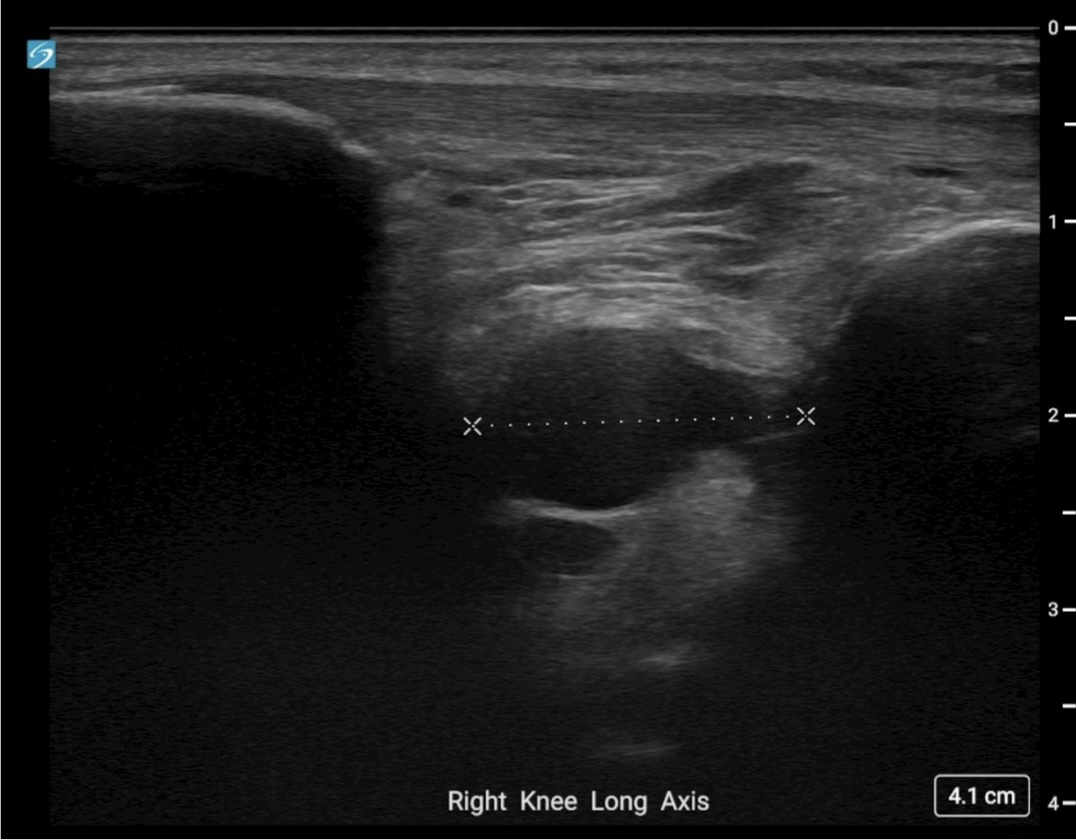

Image Interpretation: An anechoic, well-circumscribed, well-demarcated mass was noted deep to the infrapatellar fat pad. This measured 2.02 cm x 1.08 cm x 1.72 cm. No color Doppler flow was noted and the structure remained noncompressible when pressure was applied. A separate, smaller, anechoic mass was noted deeper to this structure and likely communicated with it. Findings were consistent with a multiloculated cyst of intra-articular origin.